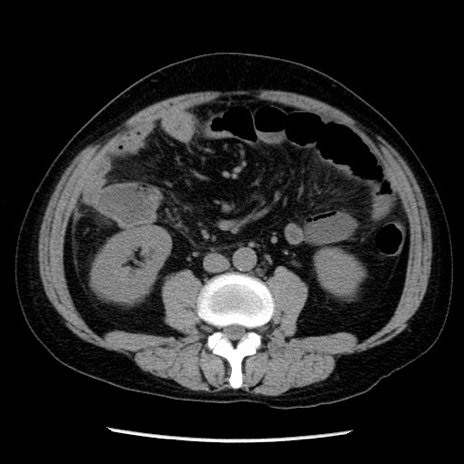

症例29(横断像)

【症例】40歳代男性

【現病歴】2日前から胃痛あり。徐々に周期的な激痛に変化した。本日になっても激痛があるため受診。

【身体所見】意識清明、BT 38-39℃台あり、腹部:膨満、やや硬、右下腹部に圧痛あり。

【データ】WBC 8500、CRP 23.26